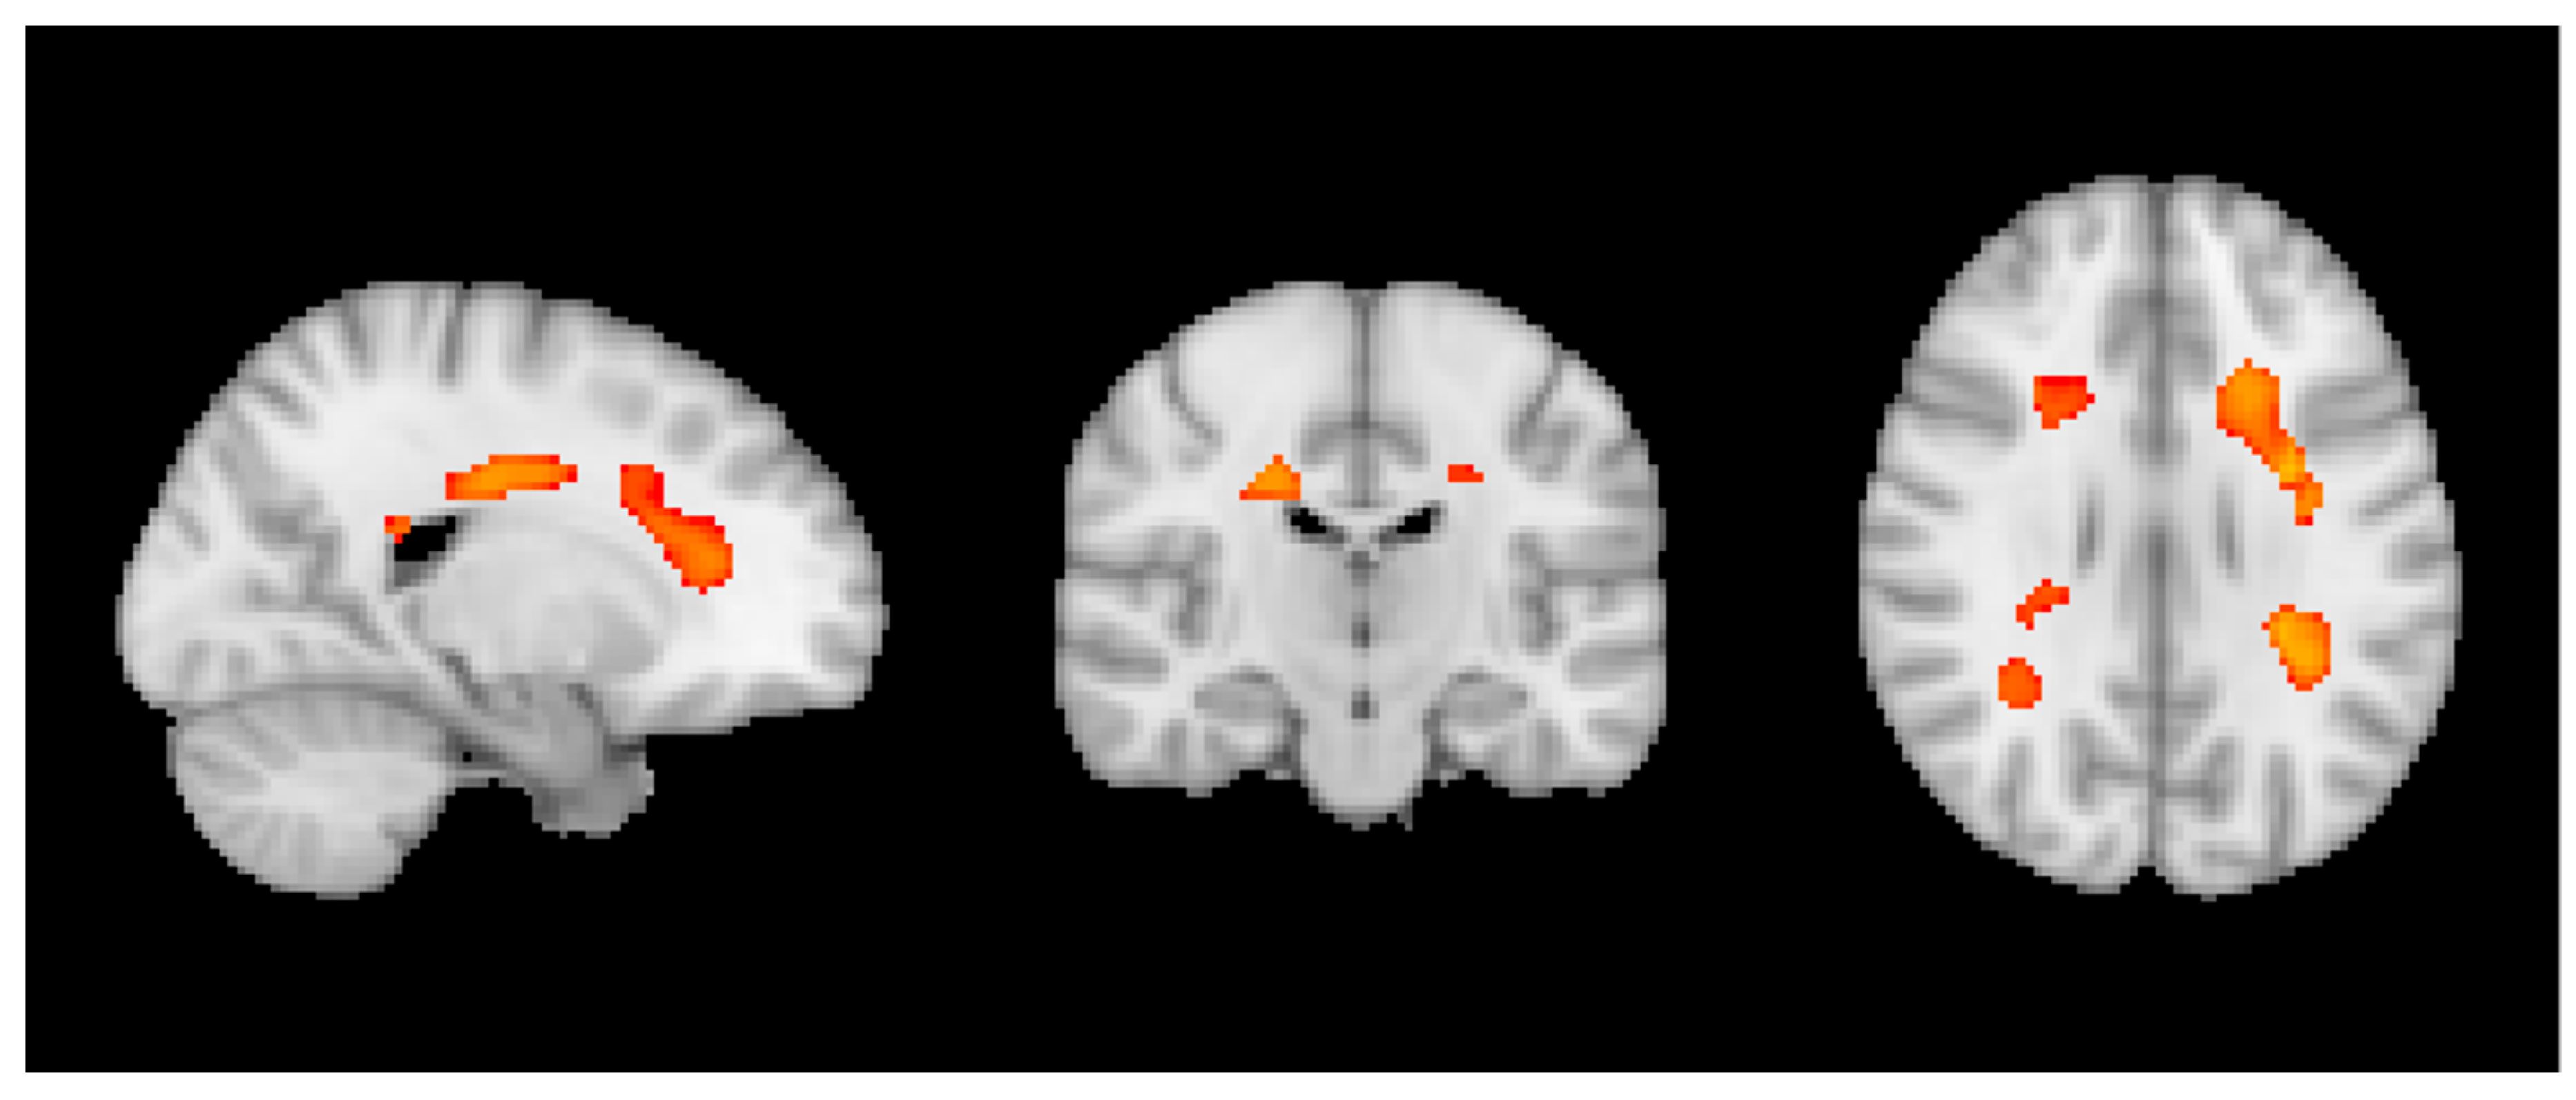

3.2. MRI Analysis across the Entire Group

3.3. Group MRI Analysis